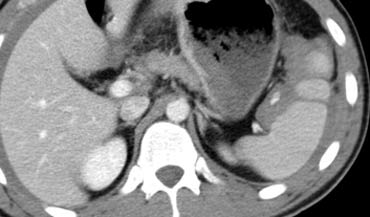

Trước tiên hãy quan sát các hình ảnh bên trái của bệnh nhân bị chấn thương gan.

Các dấu hiệu CT trong trường hợp này là gì?

Các dấu hiệu bao gồm:

- Mất tưới máu hoàn toàn thùy gan phải.

- Vùng ngấm thuốc cản quang (contrast blush) trong nhu mô gan, đồng thời lan ra ngoài bờ bên của gan.

- Tràn máu ổ bụng (Hemoperitoneum).

- Một vùng ngấm thuốc cản quang thứ hai ở mức thấp hơn.